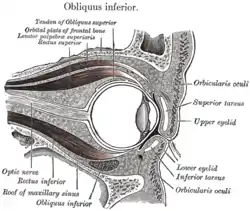

Horizontal section through the eye of an eighteen days' embryo rabbit. X 30 Sagittal section of right orbital cavity

Sagittal section of right orbital cavity Sagittal section through the upper eyelid